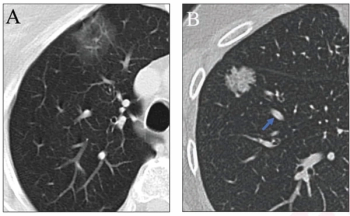

The inclusion of simulated adjudication for resolving discordant nodule classifications in a deep learning model for assessing lung adenocarcinoma on chest CT resulted in a 12 percent increase in sensitivity rate.

In comparison to standard-dose lung CT, the combination of deep learning image reconstruction with ultra-low-dose CT offered similar detection and characterization of pulmonary nodules at a nearly 93 percent reduction of radiation dosing, according to new research.